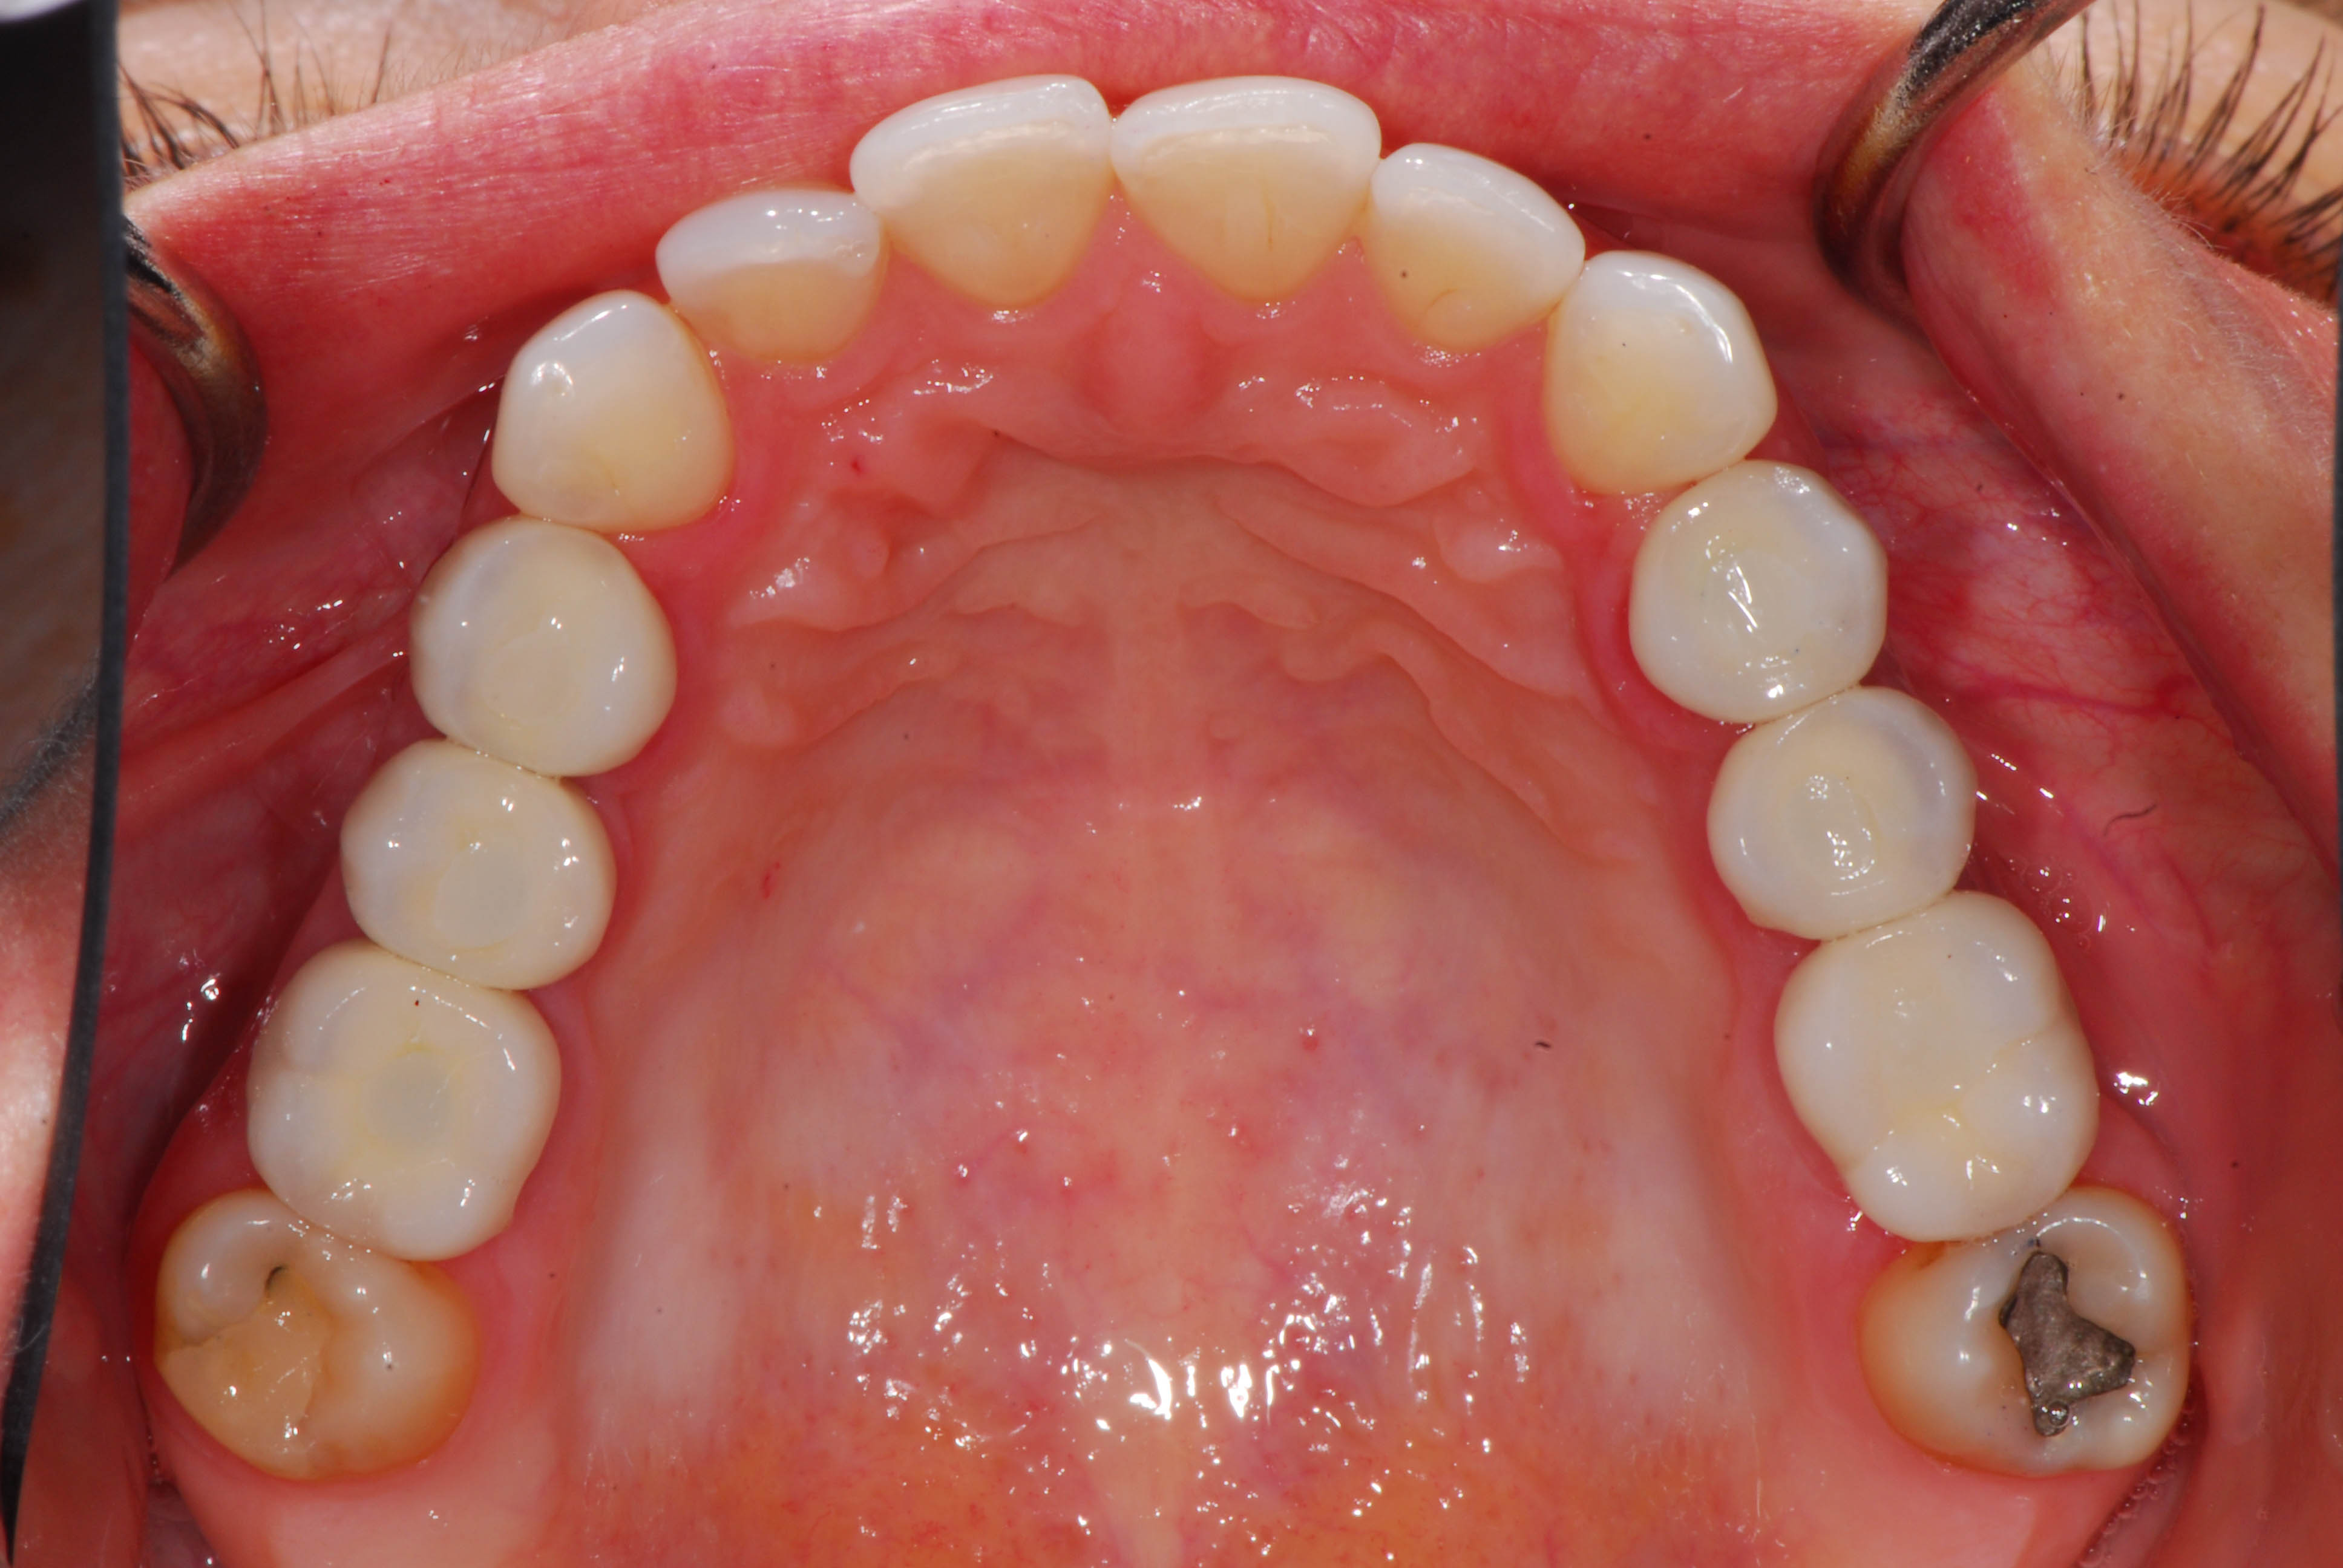

A fainting accident meant we had to replace almost all of the badly fractured upper back teeth with implant crowns.

After